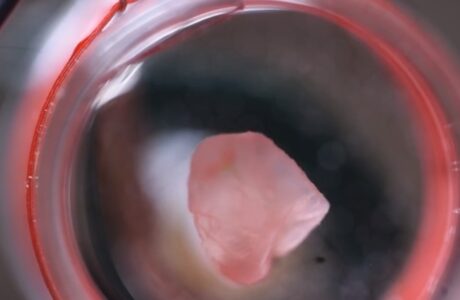

Un passo avanti importante per la biofabbricazione di organi. Ricreando la struttura elicoidale dei muscoli cardiaci, i ricercatori migliorano anche la comprensione di come batte il cuore.leggi